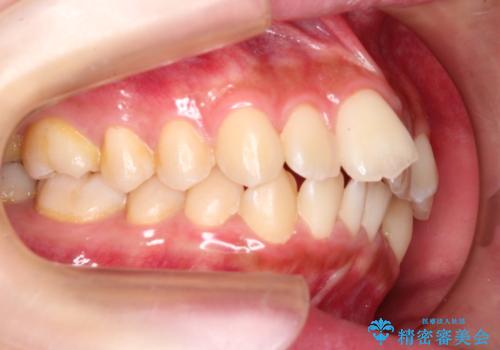

前歯のガタガタを目立たない装置でなおしたい インビザラインによる目立たない矯正

- 目立たない装置でガタガタをきれいにしたいとのご希望で来院されました。

インビザラインで矯正することとなりました。

左上の前から2番目の歯が通常とは異なる形態をしており、左右対称にすることはできませんでしたが、インビザラインで周りに気づかれることなく矯正治療をおえることができ、満足していただけました。